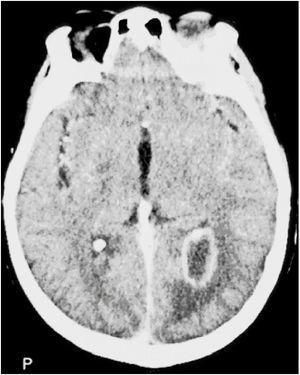

Presentamos el caso de una paciente de 47 años con poliangeítis microscópica de 8 años de evolución, en tratamiento con azatioprina y prednisona, que acude a urgencias por cefalea, náuseas y vómitos. Se diagnostica hemorragia subaracnoidea con mínima hemorragia intraventricular. La arteriografía descarta alteración vascular y se inicia tratamiento inmunosupresor con ciclofosfamida ante la sospecha de hemorragia secundaria a poliangeítis microscópica. A los 5 días presenta disminución del nivel de conciencia; se realiza tomografía computarizada (TC) en la que se observa hidrocefalia con dilatación biventricular. Se colocan dos drenajes ventriculares externos. A los 6 días de inicar el tratamiento inmunosupresor presenta fiebre elevada; se realizan cultivos de sangre y líquido cefalorraquídeo (LCR), siendo positivos para Salmonella enteritidis sensible a cefotaxima, tratamiento ya iniciado de forma empírica. Una semana después de iniciar el tratamiento, persiste Salmonella enteritidis en cultivos de LCR. Se retiran de forma escalonada los dos drenajes, cuyo cultivo fue positivo para Salmonella enteritidis al igual que el LCR obtenido. Se realiza una punción lumbar que evidencia: glucosa 35 mg/dl, proteínas 9,3 g/l y 60.267 células por microlitro de predominio polimorfonuclear con cultivo bacteriológico negativo, mientras que el LCR del ventrículo presentó glucosa 5,1 mmol/l, proteínas 2,3 g/l y células 130/microlitro. Se realizó resonancia magnética de columna que descartó absceso epidural. La TC craneal de control tras la retirada de los drenajes evidencia un absceso cerebral frontal derecho y paraventricular posterior izquierdo (fig. 1). Se procede a drenaje por punción quirúrgica, dejando catéter de drenaje izquierdo para tratamiento intratecal con amikacina. Tras 10 días de tratamiento intratecal se decide la retirada del catéter intraventricular. Ante la persistencia de fiebre alta, se recoloca el drenaje ventricular externo izquierdo y se coloca un drenaje lumbar para la administración durante 10 días más de amikacina intratecal, lumbar y endovenosa, a pesar de que los cultivos son negativos, quedando afebril a las 48 horas.

Figura 1. Absceso cerebral.